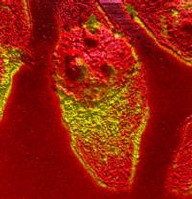

Here is an image of 3 red blood cells after exposure to an antibiotic.

Yellow represents where the cell membranes are disrupted or interacting with the antibiotic.

This image can help further visualize the effect detergents can have on cells.